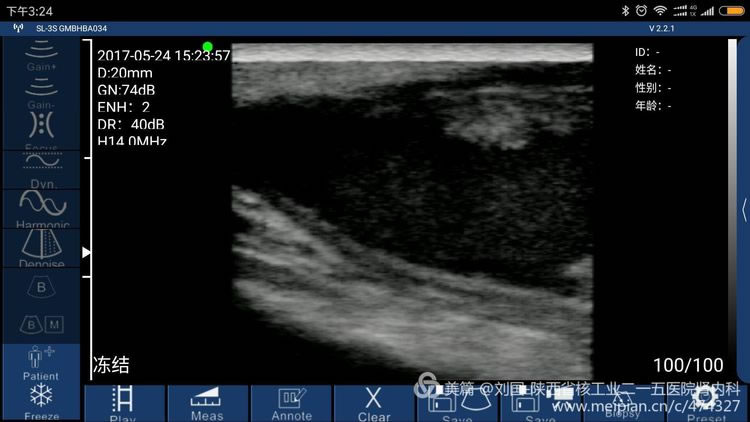

Result checked by Sonostar’s wireless ultrasound, and displayed by my mobile phone-Mi max

Cephalic vein condition checked by Sonostar’s wireless ultrasound, and displayed by my mobile phone-Mi max